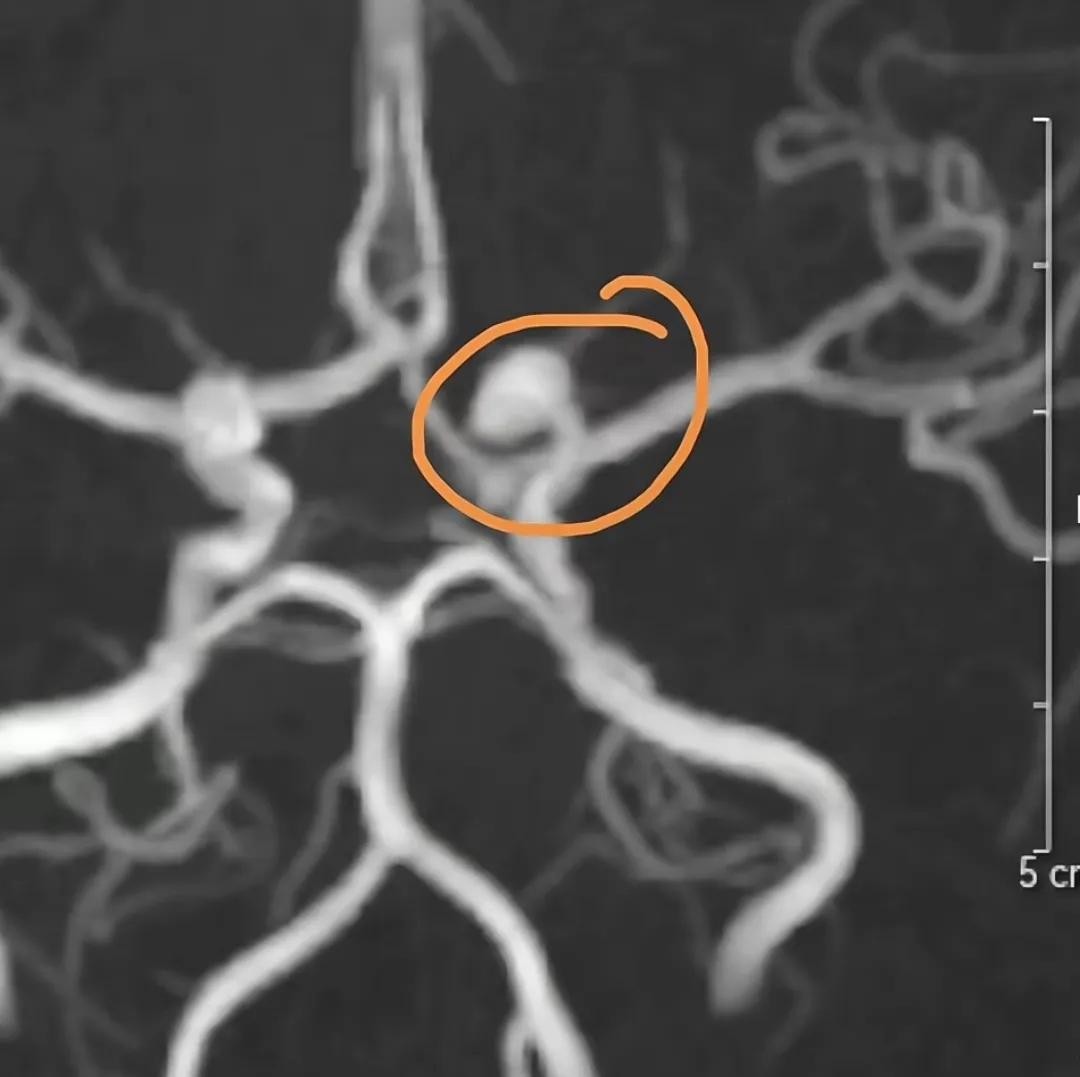

今年1月15日,孙铱在个人社交账号上发布了一条令人揪心的消息:她确诊了脑动脉血管瘤。血管瘤虽然暂时没有影响她的正常生活,但医生告诉她,这个瘤体存在引发脑血栓的风险,必须尽快进行手术。